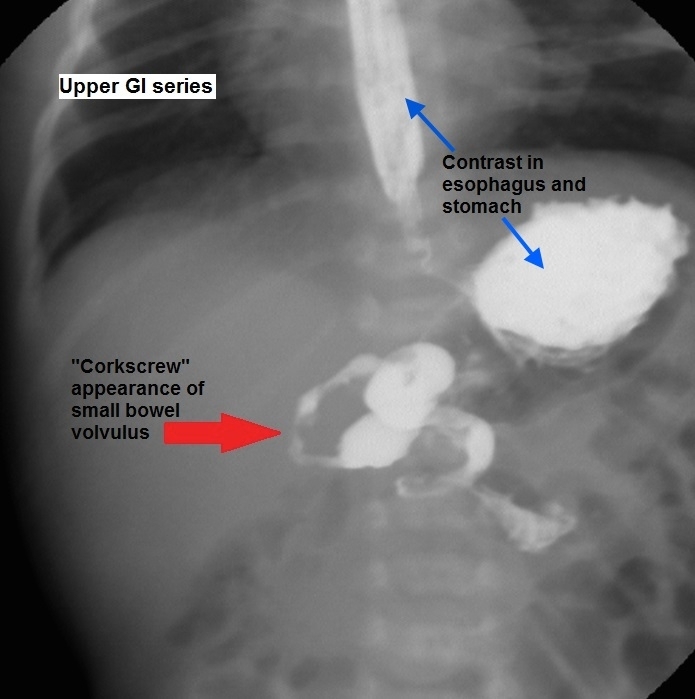

Volvulus

The finding of the Ligament of Treitz on the right side of the abdomen reflects malrotation while contrast in a "corkscrew" pattern indicates volvulus.